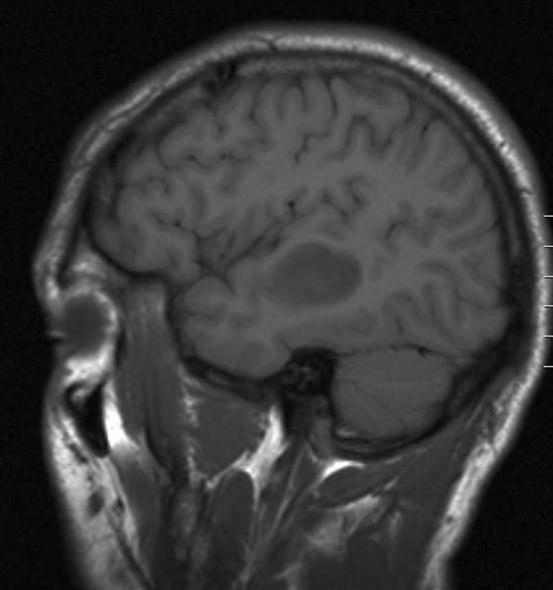

Lavgradig astrocytom, sagittalt snitt

Lavgradig astrocytom WHO grad II

Gjengitt med tillatelse av Radiologisk avdeling, Universitetssykehuset Nord-Norge